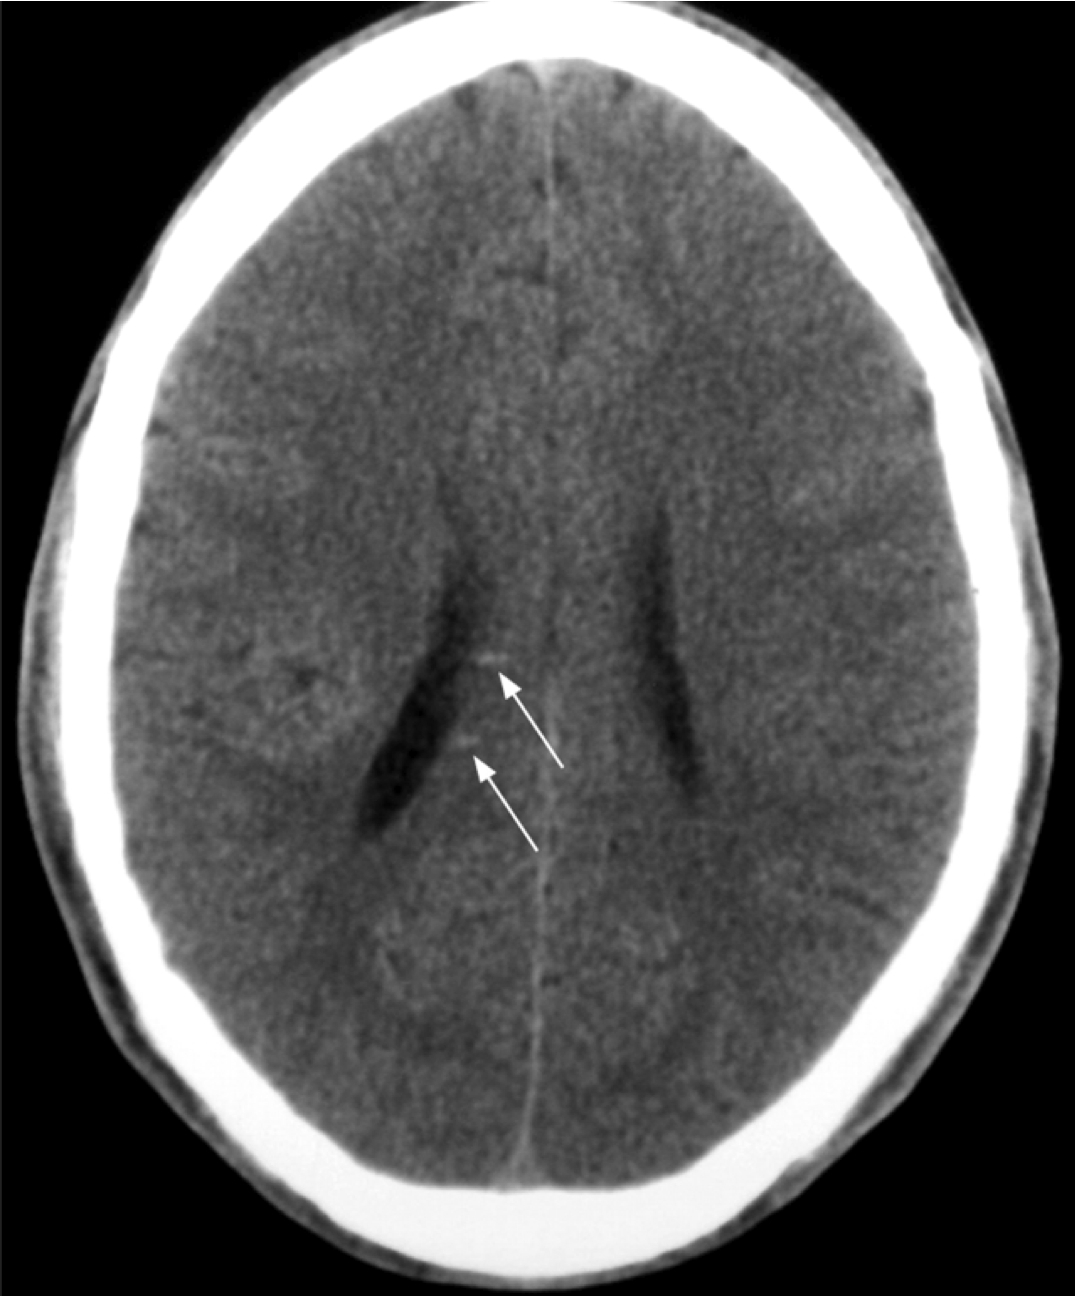

Normal Brain vs. Atrophy Secondary to Axon Shearing Injury